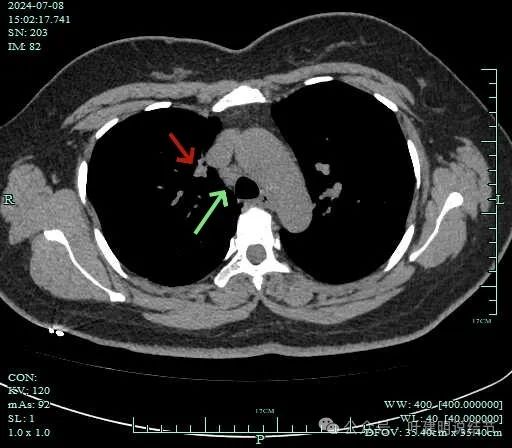

再看2024年7月份的影像:

毛刺征明显,灶边细支气管扩张。

病灶整体轮廓还是较为清楚的。

病灶边支气管可见。

病灶小,但有一定收缩感。